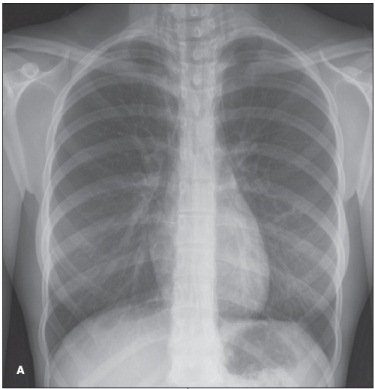

spontaneous pneumomediastinum

Lisa M. Clewner, MD

<p><img src="/sites/default/files/transfer/1202CFP_PCPneumo_A_thumb.jpg" width="87" height="90" style="float: left; margin:...